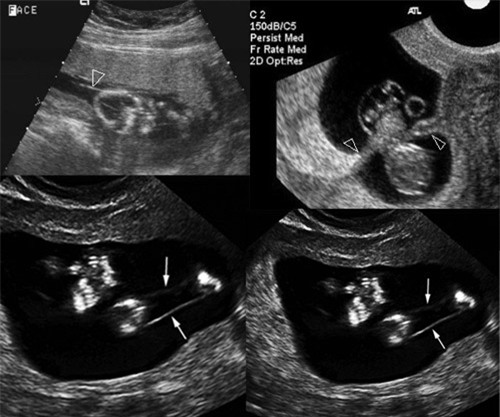

Hiện tượng dải sợi ối được phát hiện thông qua siêu âm. Những điểm có dải sợi ối được đánh dấu bằng mũi tên

Phát hiện mẹ bầu có bị dải sợi ối hay không là dựa vào siêu âm hình thái có thể thấy được em bé có bị dị tật hay không. Vì vậy, với những mẹ rơi vào trường hợp hợp này cần phải đi khám thai thường xuyên để được theo dõi kỹ lưỡng.